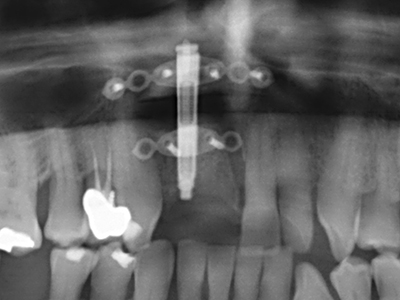

Когато се извършват хирургични процедури върху кост в непосредствена близост до чувствителни структури като кръвоносни съдове или нерви, ротиращите инструменти създават значителен риск за ятрогенно нараняване. Пиезоелектрическите апарати могат да бъдат от помощ при препарация на костно покритие и отстраняване на твърда кост близо до нерви, особено за оголване на нервите след ятрогенно нараняване, както и по време на латерализация на нервите за резекционни и реконструктивни процедури или поставяне на имплант (Фиг. 17-20). Лекият контакт между пиезонакрайника и нерва по принцип не води до нараняване, но ако действате непредпазливо с трионообразни движения или приставки за остатъчен костен субстрат, може да причините временно или перманентно увреждане на нерва. Въпреки това, рискът от увреждане се счита за много по-малък, отколкото при употреба на триони или ротиращи инструменти (Pereira, Gealh et al. 2014).

Както е показано в миналото, всяка костна хирургия представлява възможна индикация за пиезохирургия. По този начин, за препарацията на подвижни сегменти в остеогенеза (Фиг. 23-25) и остеотомия се използват специални накрайници, без да се застрашава снабдяването с кръв в кресталната зона, което е от съществено значение за успеха и на двете техники (Gonzalez-Garcia, Diniz-Freitas et al. 2008).

За отстраняването на имплант, вестибуларното костно покритие, което е заменено след премахване на импланта, може да бъде оформено, за да задържи контура на алвеоларния гребен.